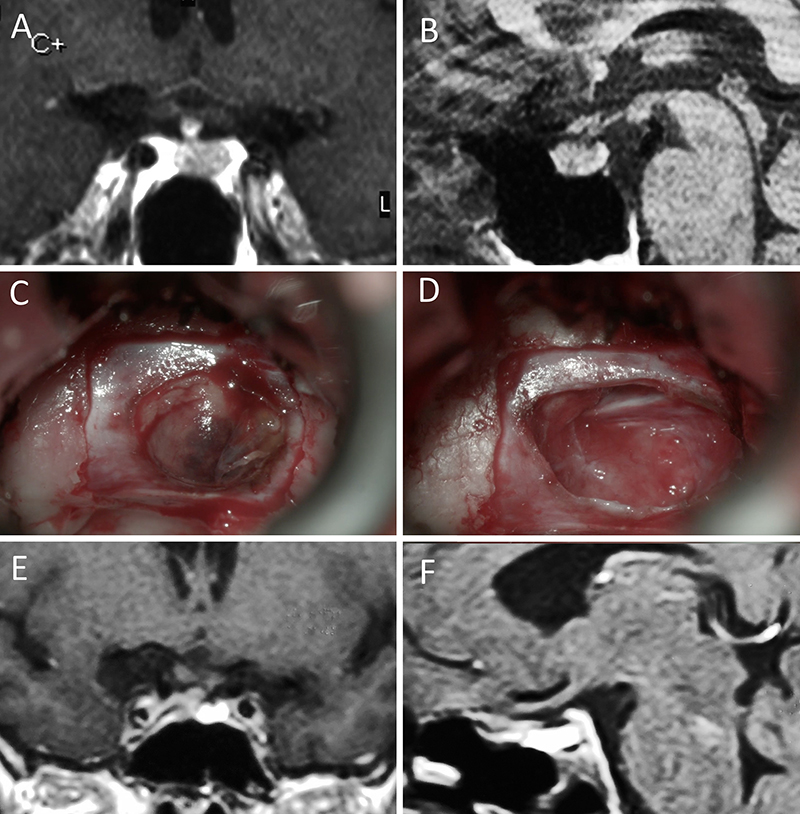

Figura 3: Macroadenoma no funcionante en un hombre de 64 años. El paciente presentó en el preoperatorio déficit visual que mejoró tras la cirugía. A-B: RM preoperatoria; C-D: intraoperatorio; E-F: RM postoperatoria.

Figura 4: Macroadenoma no funcionante en mujer de 32 años. La paciente presentó en el preoperatorio déficit visual que mejoró tras la cirugía. A-B: RM preoperatoria; C-D: intraoperatorio; E-F: RM postoperatoria.